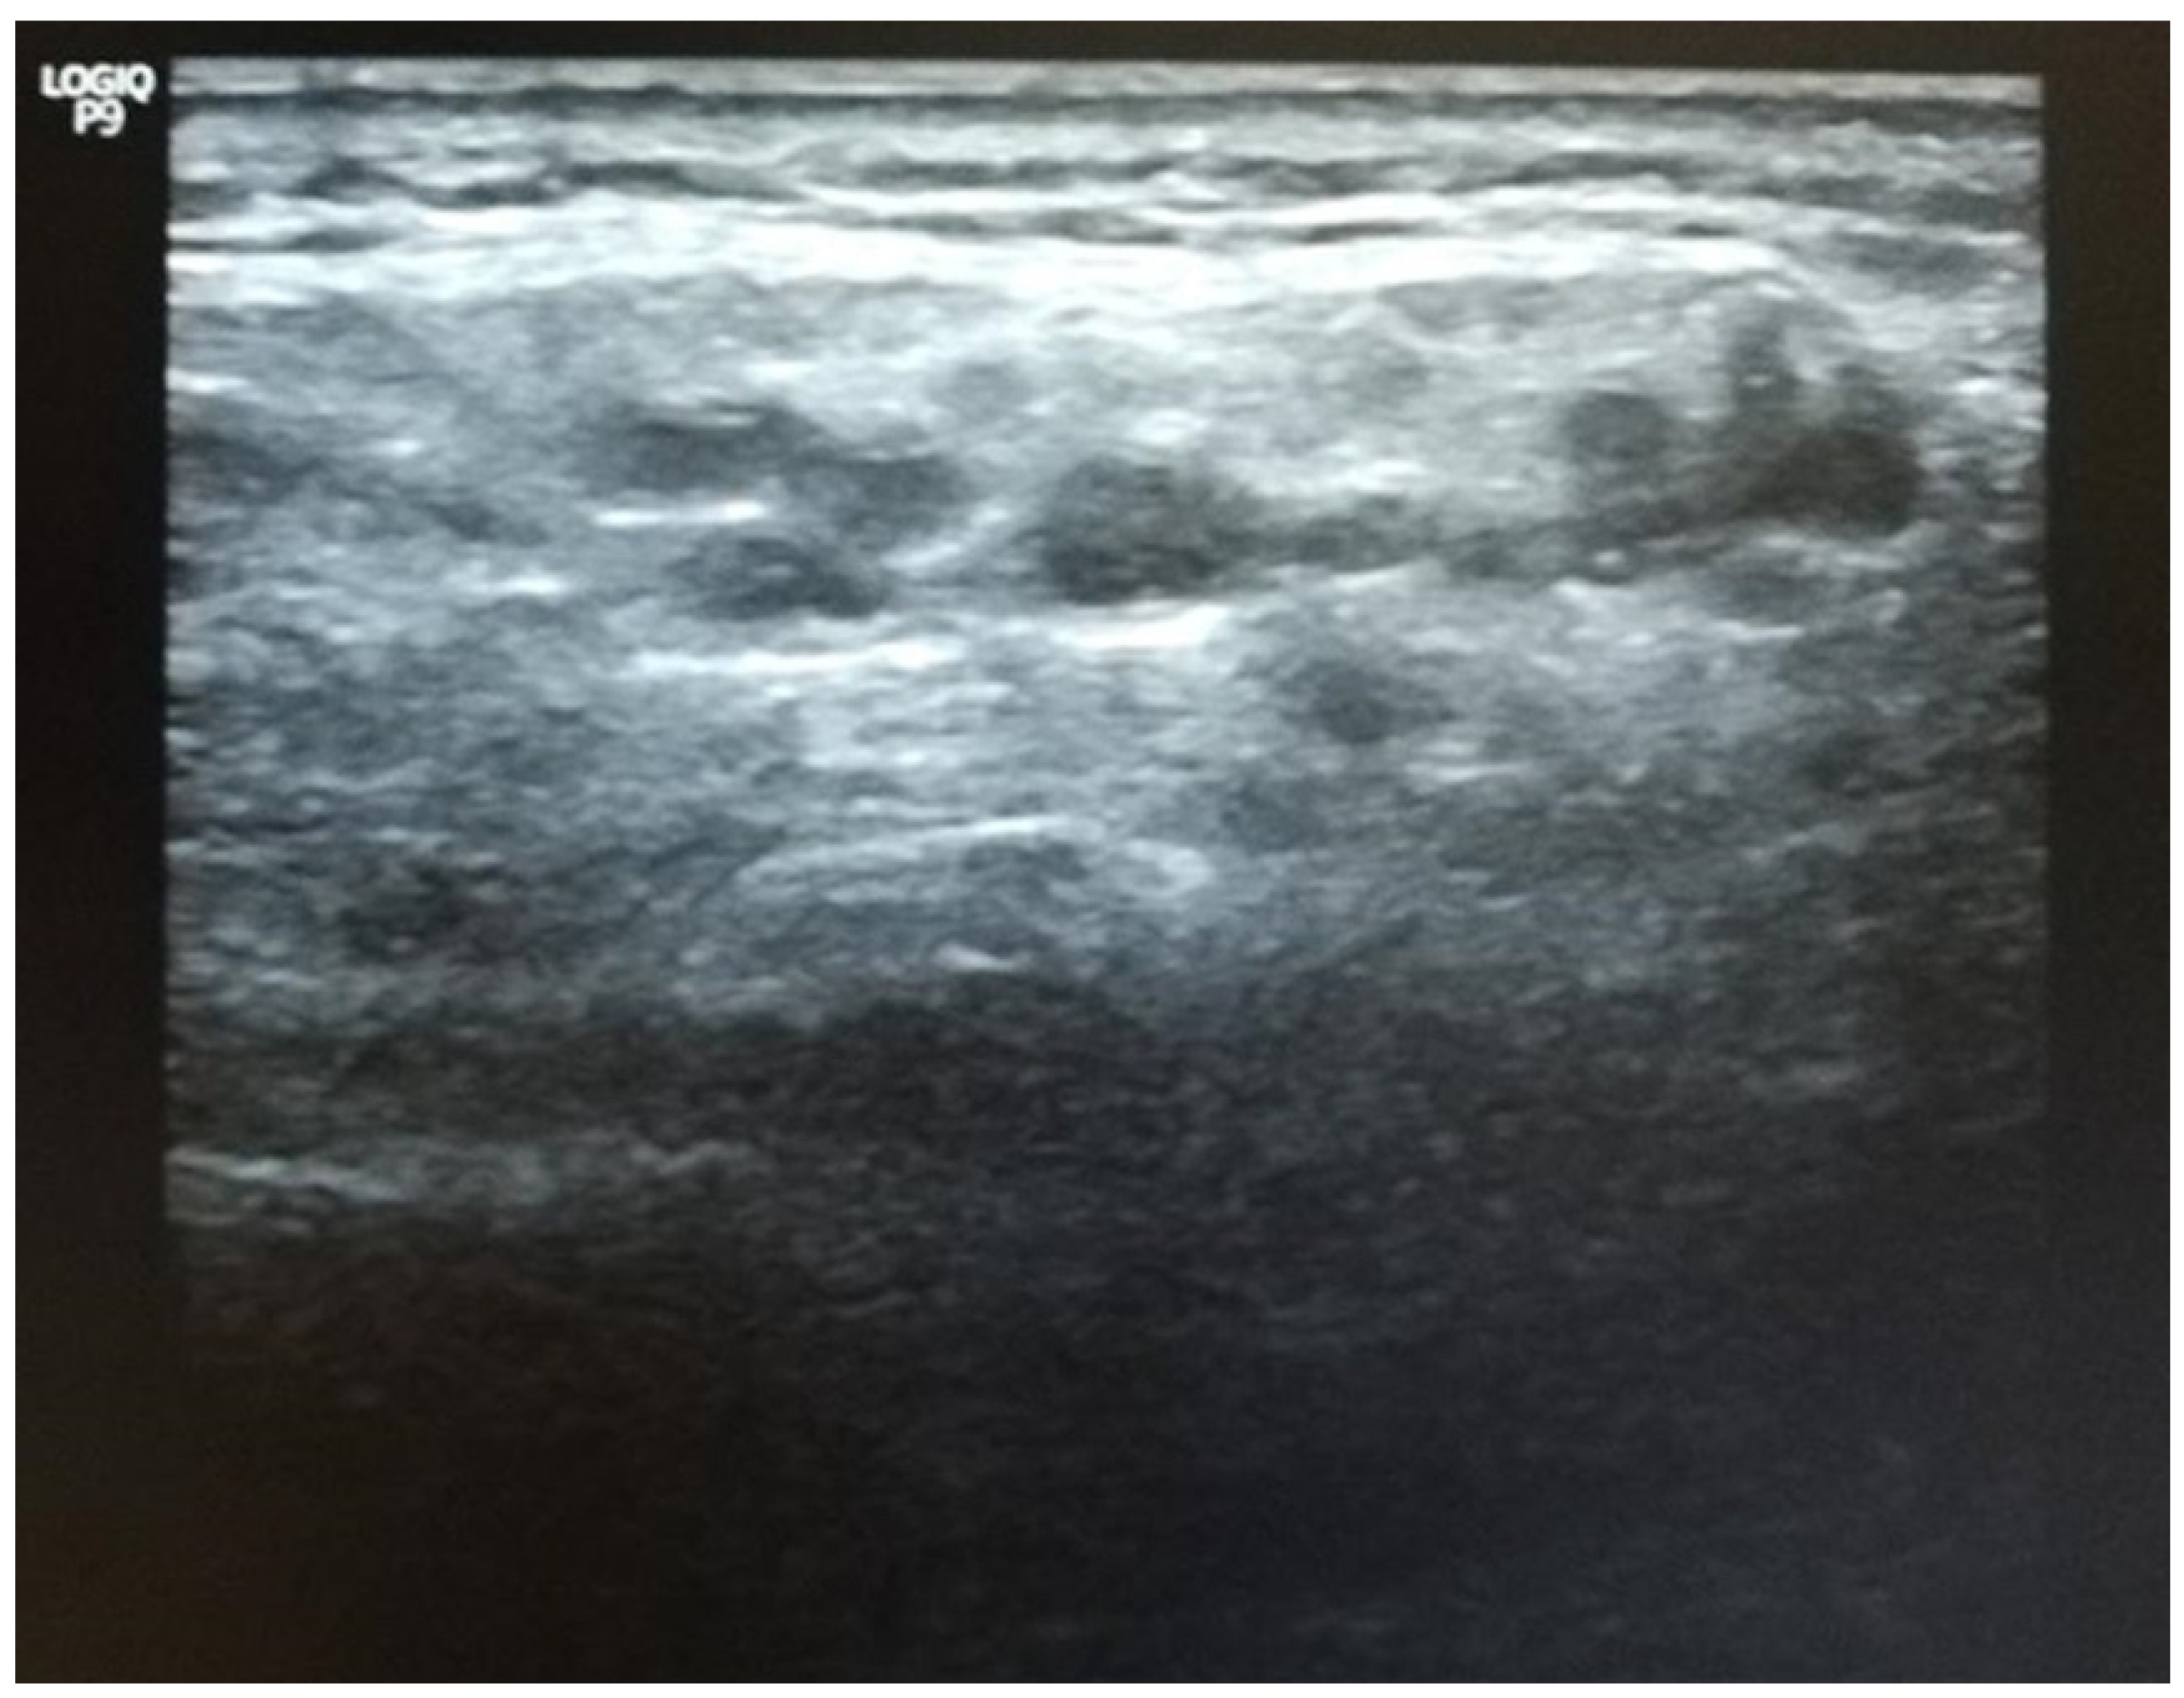

- Jousse-Joulin, S.; D’Agostino, M.A.; Nicolas, C.; Naredo, E.; Ohrndorf, S.; Backhaus, M.; Tamborrini, G.; Chary-Valckenaere, I.; Terslev, L.; Iagnocco, A.; et al. Video clip assessment of a salivary gland ultrasound scoring system in Sjögren’s syndrome using consensual definitions: An OMERACT ultrasound working group reliability exercise. Ann. Rheum. Dis. 2019, 78, 967–973. [Google Scholar] [CrossRef] [PubMed]